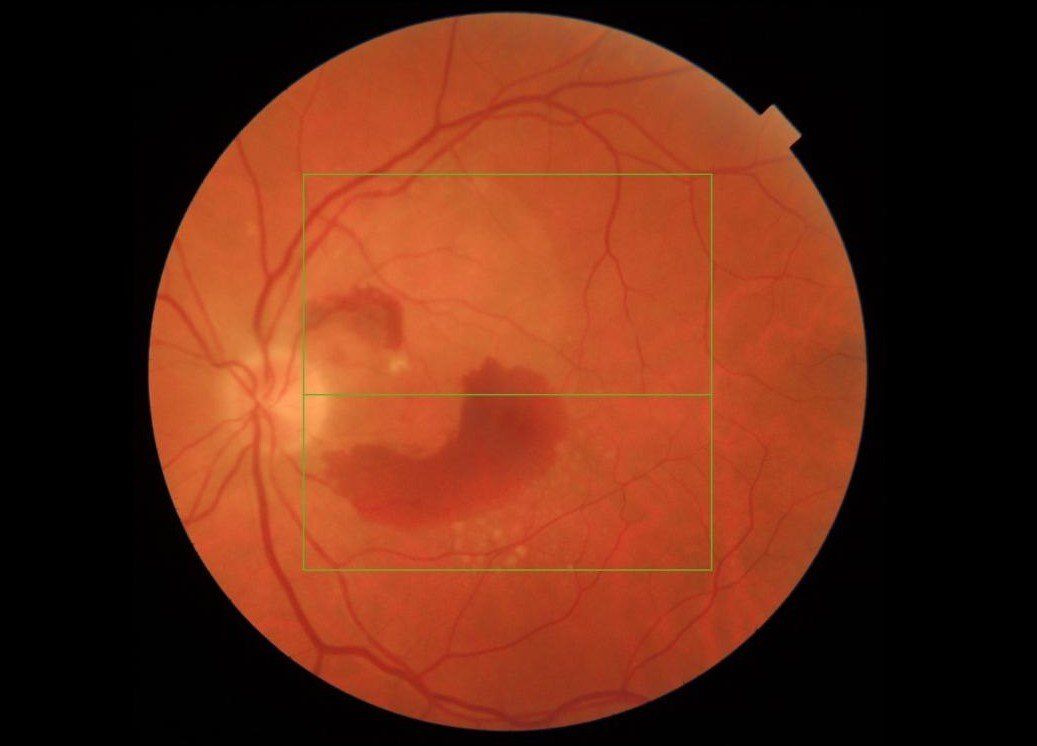

Wet age-related macular degeneration (AMD)

- This occurs when there is a buildup of fluid in the underlying layers of the macula, secondary to degeneration of the cells that process light.